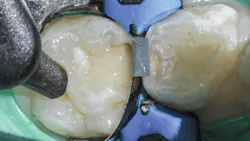

A selective-etch technique with 35% phosphoric acid is used to achieve the highest possible bond strengths.6,7 The etchant is washed and the tooth is dried without desiccating it. A universal bonding agent (Futurabond U, Voco) is rubbed onto the tooth surface for 20 seconds (figure 3), and thenThis is a modified snowplow technique, in which the flowable base layer is light cured in combination with placement of 4 mm of the restorative material.8,9 This allows the flowable to extrude up to the occlusal surface and down to the gingival margins, filling any voids.

The restorative material is warmed first in a Caps WarmerNano-ORMOCER materials provide clinicians with an excellent restorative option for pediatric patients that can appease concerned caregivers without disrupting current workflows. No doubt public scrutiny of our restorative materials will continue, whether their conclusions are legitimate or ill-informed. But we will also continue to see children with dental caries, so we would do well to add new materials to our armamentarium that can support good oral health outcomes and reassure caregivers of their safety.